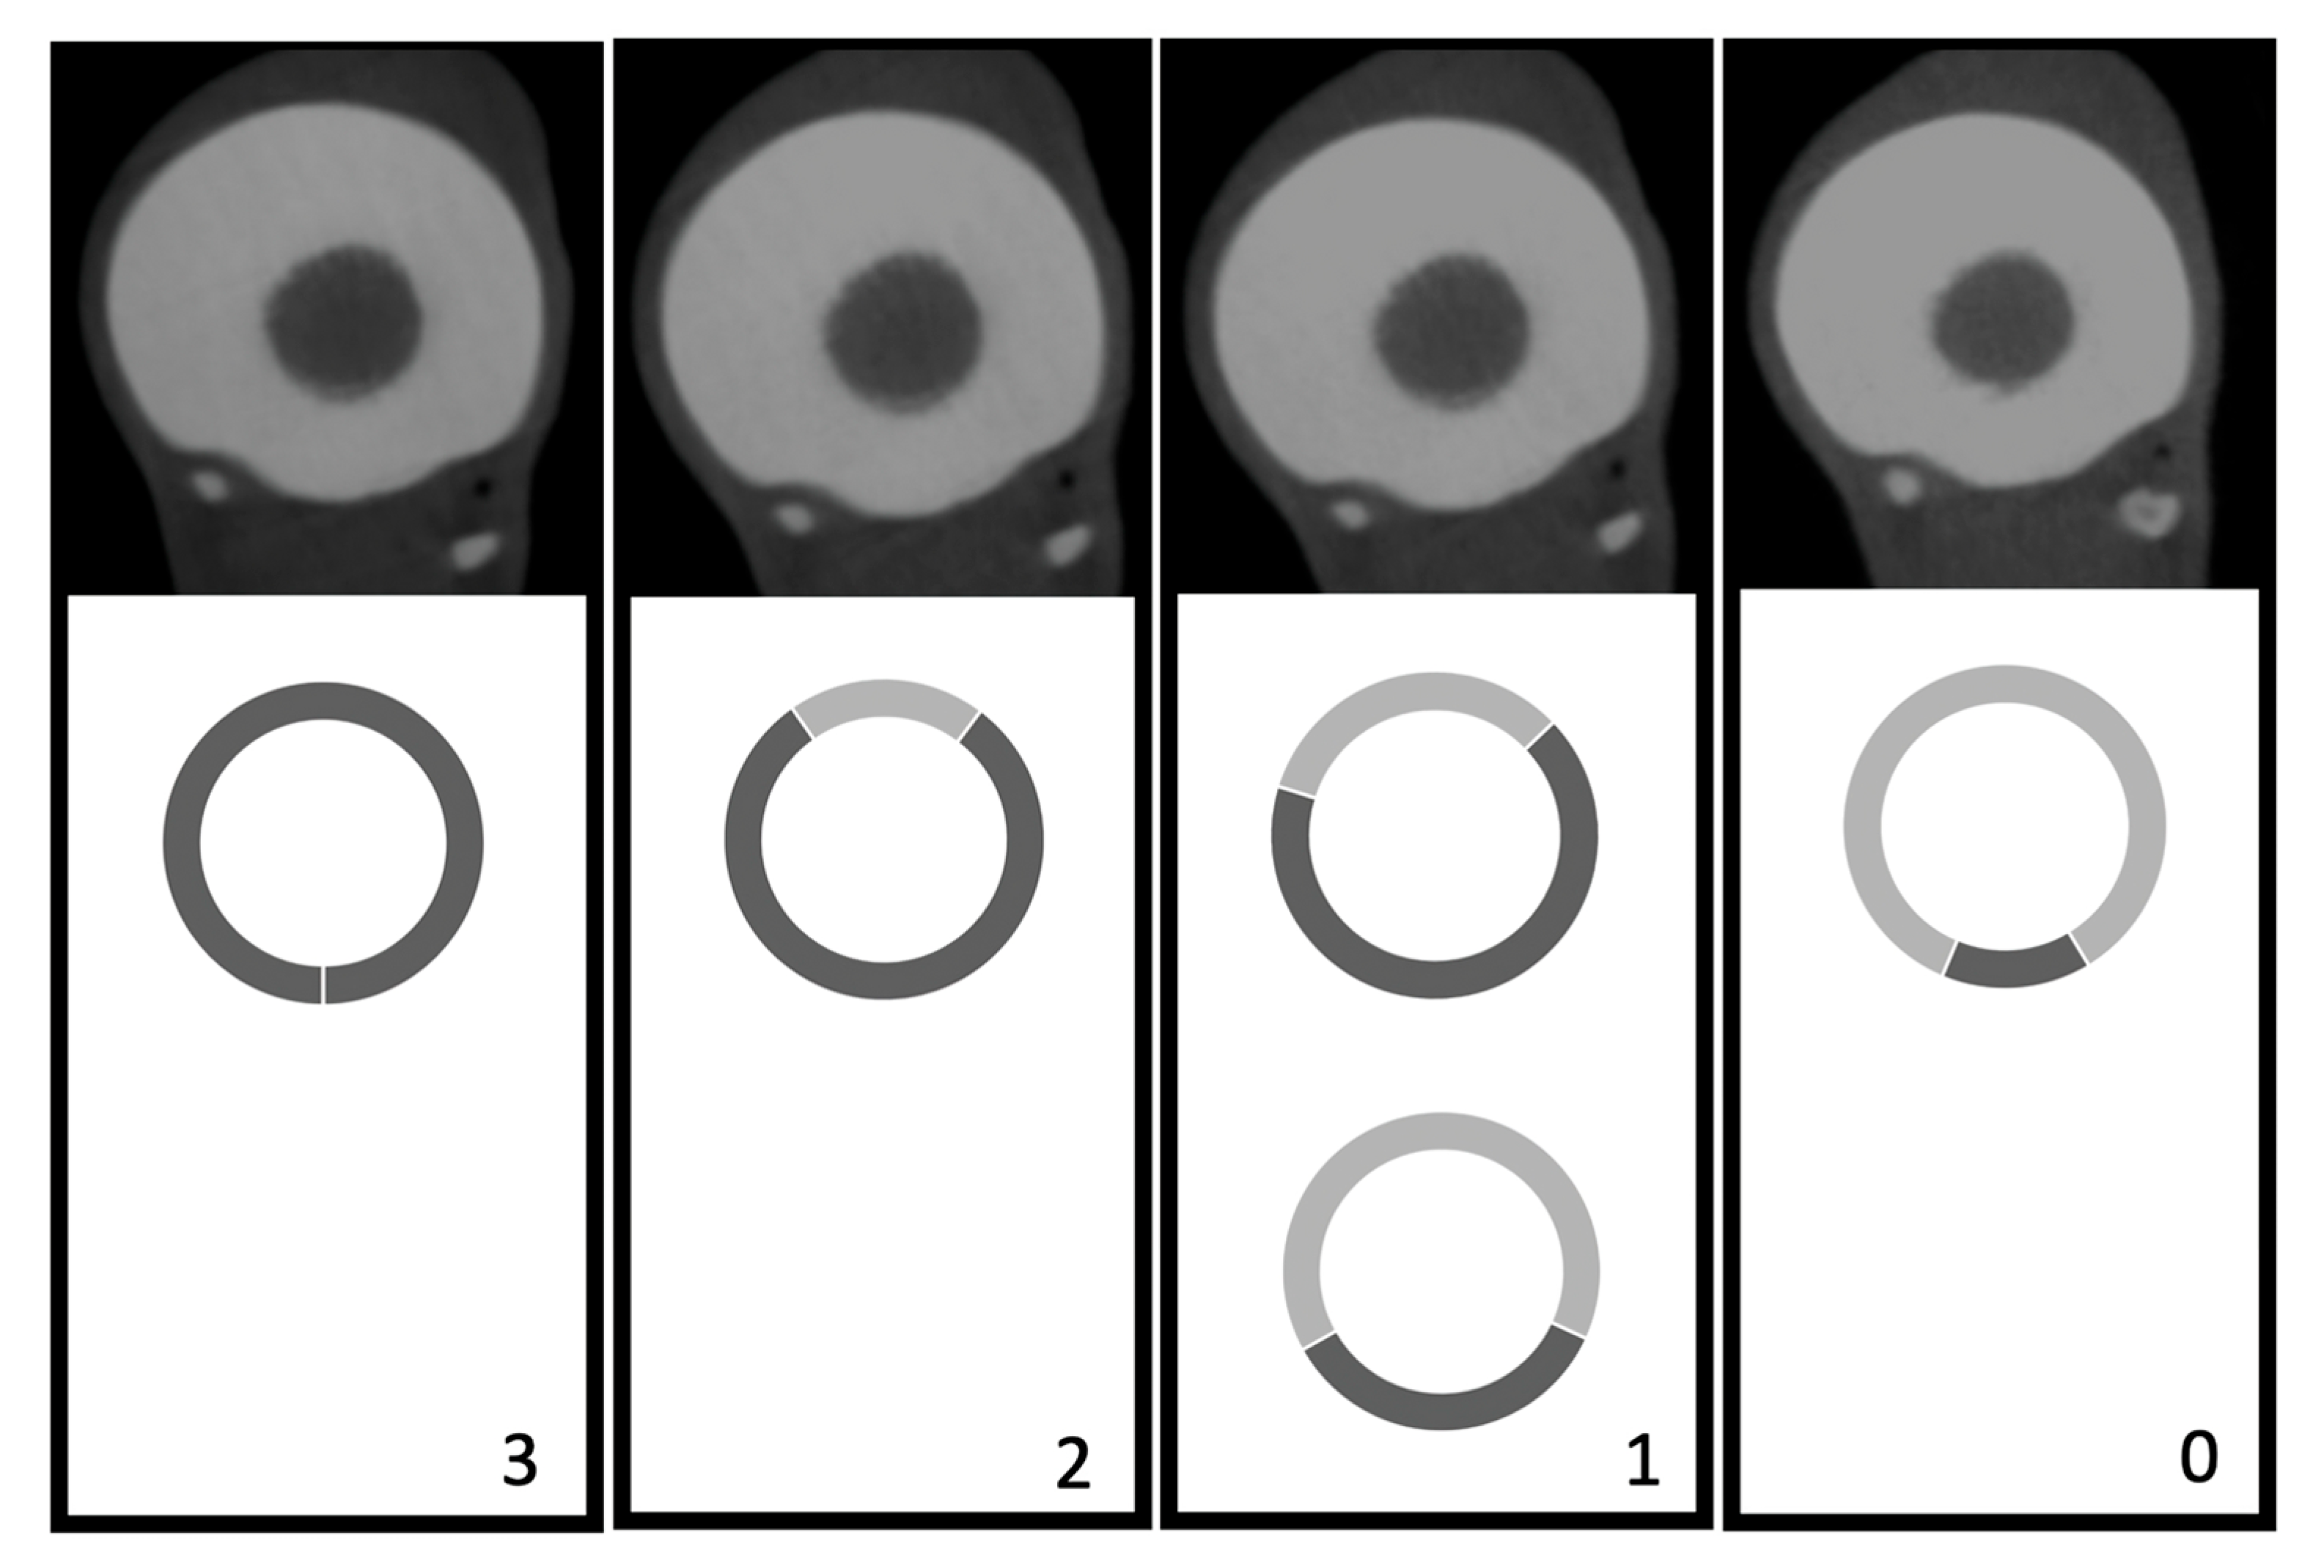

2.2.1. Visual Image Quality Assessment

3.1. Visual Image Quality Assessment

3.2. Clinical Case–Visual Image Quality Assessment